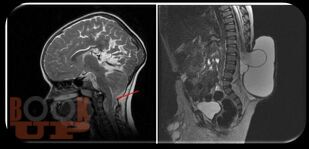

Аномалия Арнольда-Киари

В нем освещены вопросы патогенеза, современные принципы диагностики, лечебные тактики и клинические исследования пациентов с аномалией Арнольда-Киари. Пособие снабжено тестовыми заданиями и ситуационными задачами с эталонами ответов. Предназначено для обучающихся по программе ординатуры по специальности 31.08.56 Нейрохирургия.